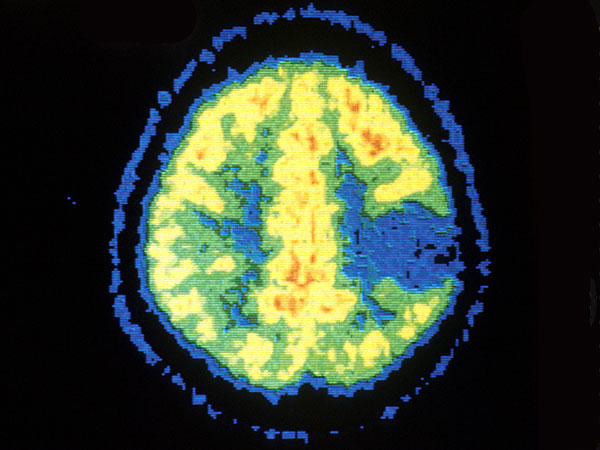

PET scan showing astrocytoma.

Credit: National Cancer Institute